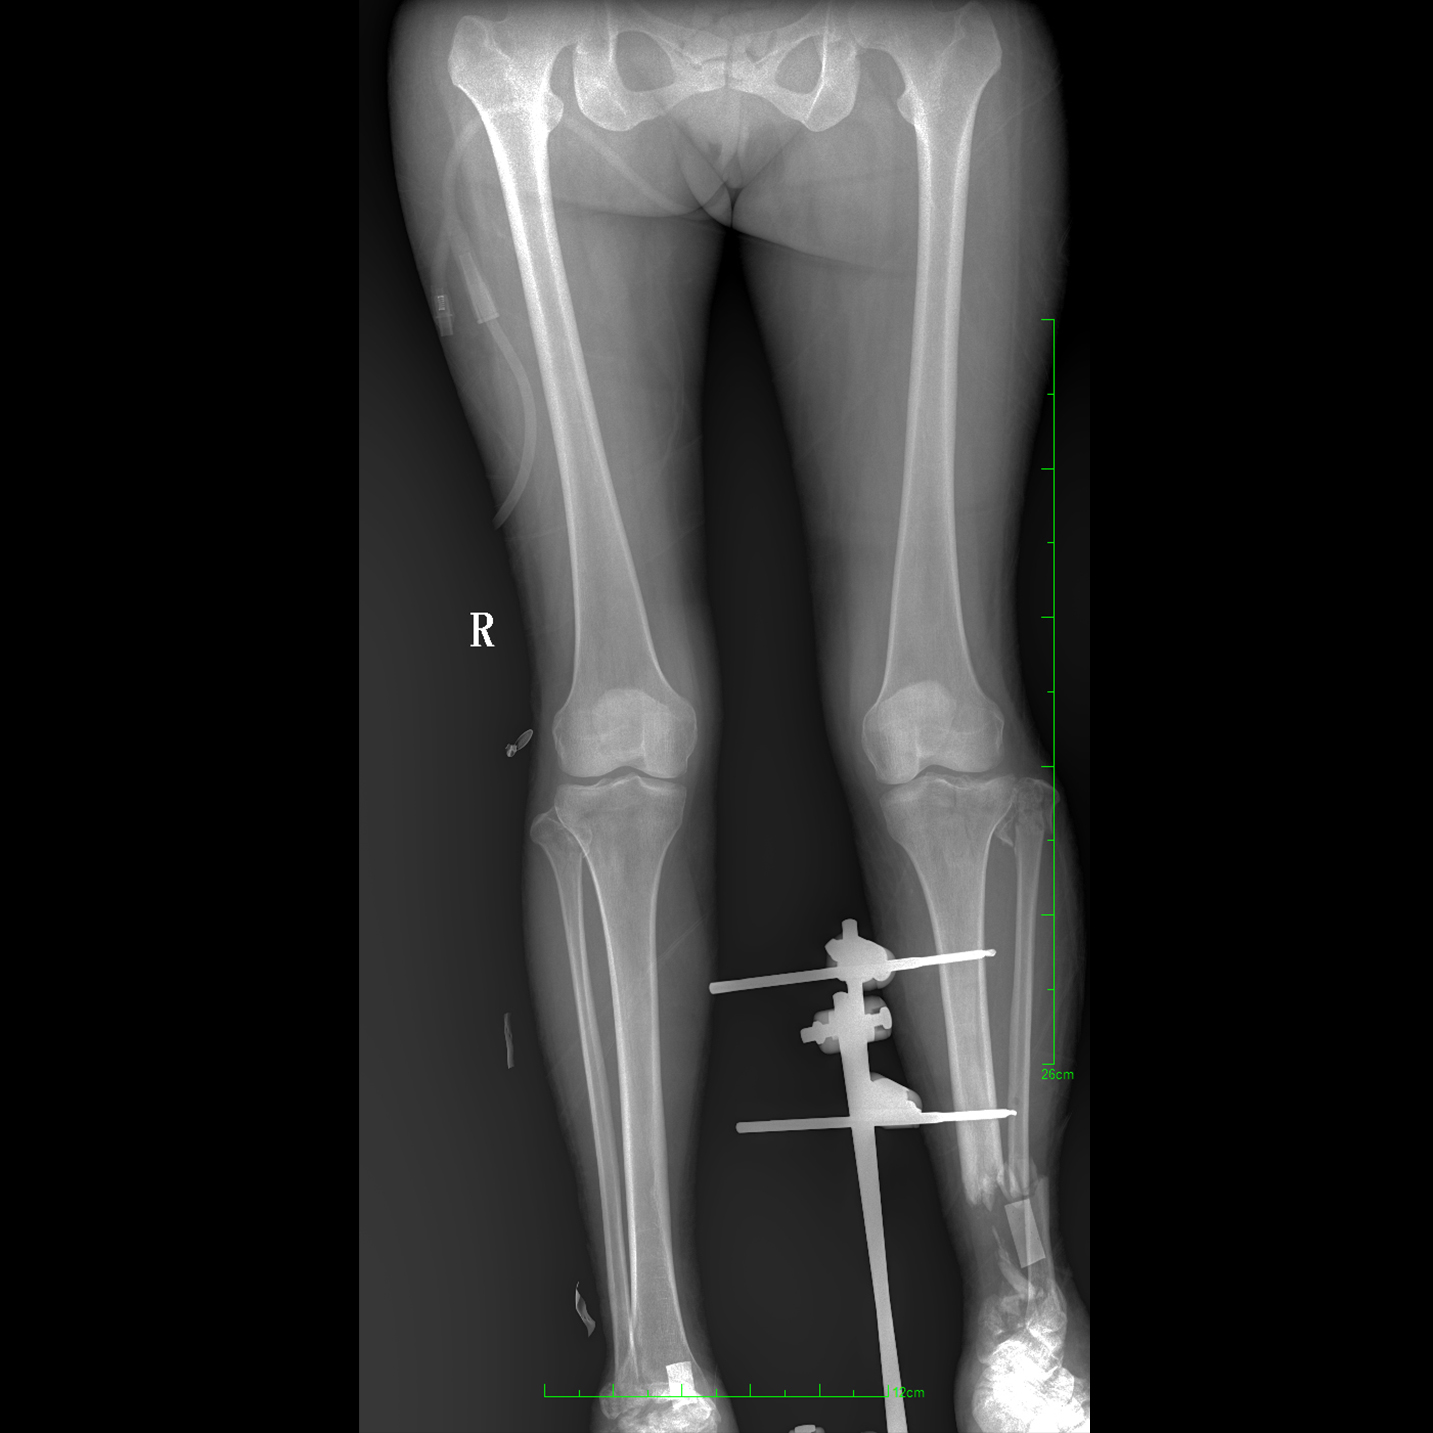

支持全脊柱攝影、雙下肢攝影、脊髓造影、復雜創(chuàng)傷、人工關節(jié)置換、關節(jié)損傷的修復重建等大視野臨床應用

17"*34"有效視野,一次成像不拼接。相較于多張攝影再軟件拼接的DR設備,PLX8600解決了拼接圖像存在密度不均勻,拼接處圖像配準和放大效應等問題,給臨床帶來了大視野影像解決方案,可一次性覆蓋全脊柱或雙下肢影像。